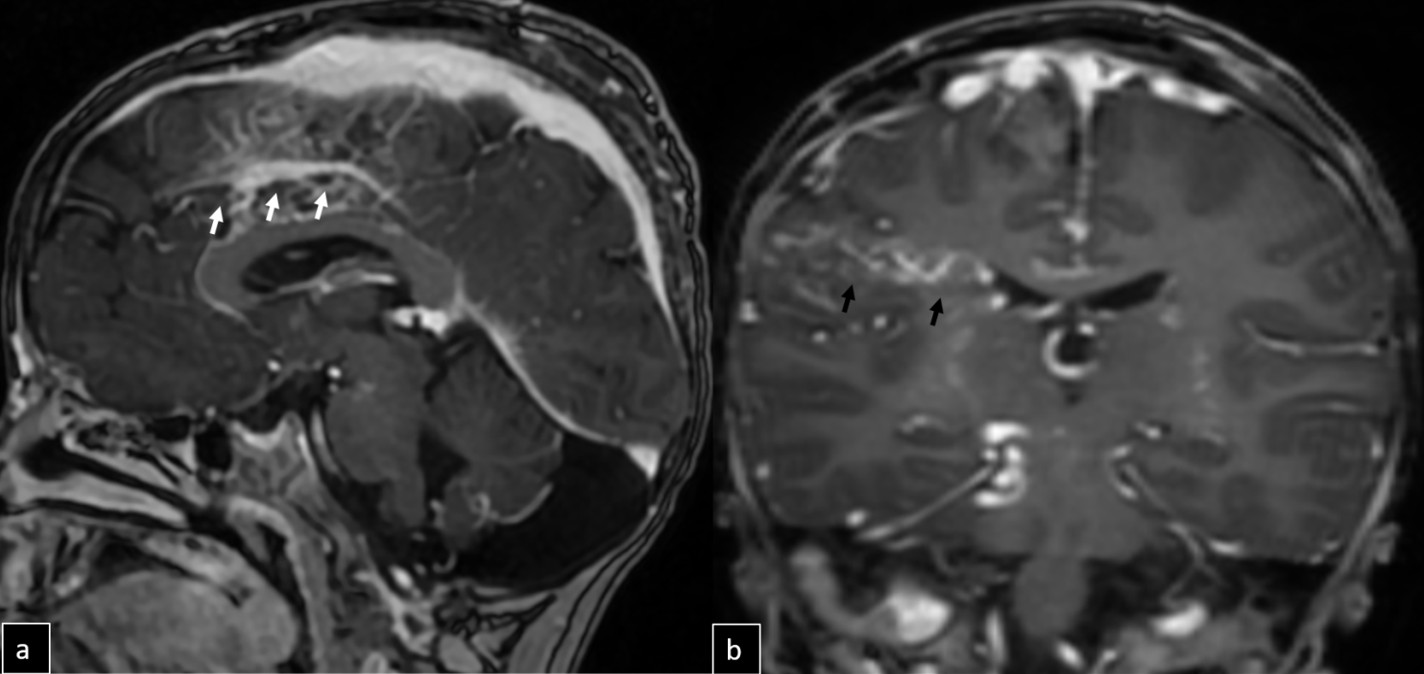

Cranial MRI demonstrated a dilated tortuous arteriovenous malformation in the right frontal lobe, fed by the distal branches of the anterior cerebral artery (ACA), draining into the cortical veins and central nervous system. A second AVM was detected in the corona radiata, with dilated parietotemporal draining veins fed by perisylvian branches of the middle cerebral artery (MCA), draining into the internal cerebral veins and the straight sinus via pericallosal dilated venous structures (Figure 2, Figure 3, Figure 4). At the level of the basal ganglia and mesencephalon, arterial angiomatosis resembling the classic “moyamoya” appearance was observed (Figure 5).

Digital subtraction angiography (DSA) confirmed the presence of two AVMs: one fed by distal branches of the right ACA and draining into the superior sagittal sinus, and another fed by MCA branches, draining into the internal cerebral vein. Capillary anastomoses were noted between the two AVMs. Selective bilateral internal carotid artery (ICA) injections revealed globally abnormal, tortuous arteriolar networks with delayed capillary filling, more pronounced on the right side (Figures 5, Figure 6, Figure 7). Based on these findings and the revised 2021 diagnostic criteria, the patient was diagnosed with MMD—characterized by stenosis of the intracranial ICA, narrowing at the terminal portion, and the development of abnormal collateral networks in the basal ganglia and periventricular white matter.4